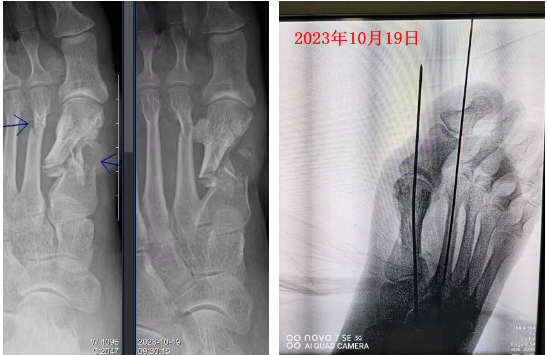

2023年10月19日,59岁的赵大姐在田地劳作时不慎被农机伤及左足,当场血流不止!赵大姐及家属直接慌了神,120紧急送至阜阳市第六人民医院。

接诊医生查视赵大姐的伤情并行X线检查后诊断:左足开放性粉碎性骨折;左足部皮肤脱套伤。

急诊科完善术前准备后,急诊行“开放性骨折复内钢针内固定术+血管神经肌腱探查修复+足部套脱皮肤原位回植术+VSD持续负压引流术。”

由于损伤过重,赵大姐足面的撕脱回植皮肤没能存活。经医生努力,创面反复清创后,使用抗生素骨水泥填充处理,于2023年11月1日经患者同意,在急诊科、超声科、麻醉科等多科室的通力配合下,成功将赵大姐的股前外侧游离皮瓣移植至其左足背部,以此来修复左足背部创面,保全了赵大姐的左足。